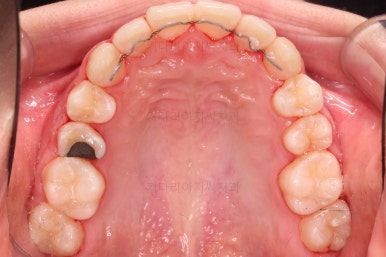

장치를 처음 부착한 사진입니다.

이번 환자분은 특징적으로 윗니의 장치와 아랫니의 장치가 다르죠.

윗니는 좀 더 심미적인 세라믹으로 선택하셨고 아랫니는 비교적 저렴하고 부피가 약간 작고 튼튼한 메탈로 진행했습니다.

그래도 됩니다.

심지어는 같은 회사 제품이 아니더라도 적절하게 세팅을 고려하면 섞어 사용하는 것도 가능하답니다.